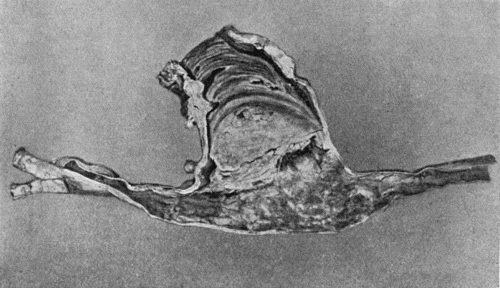

168.Multiple partially ossified Chondromas of Synovial Membrane from Shoulder-joint 542

169.Multiple Cartilaginous Loose Bodies from Knee-joint 543